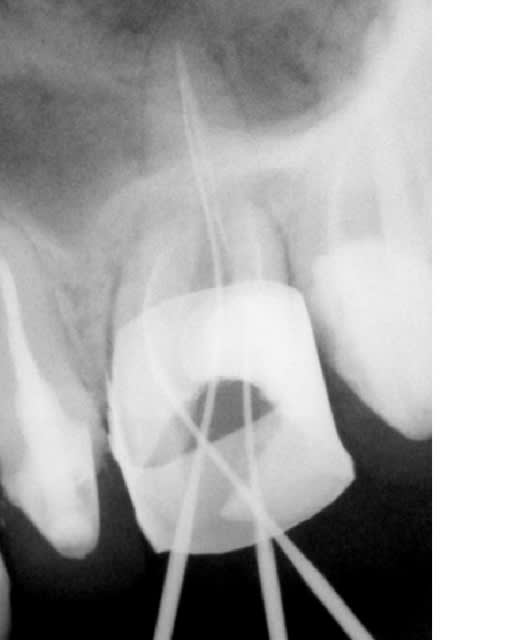

Curieusement je n'ai eu que 3 endos depuis, reprises sur 2 centrales et 1 reprise sur une 26.... 1 a été obturée et les 2 autres sont en cours (durailles les sagouines).

ps: steph comment tu géres la digue et la bague de cuivre.... j'ai dechiré 3 feuilles avant d'abandonner pour la molaire et donc j'ai partiellement desobturé cette fichue 26 mais pas "comme il le faudrait", et j'ai recommandé des boites de digue pasque du coup j'ai épuisé le stock.

ps j'ai bien localisé un mv2 "oublié" par mon predecesseur mais macache pour le cateteriser; comme il semble en continuité anatomique avec le mv1 (y'a comme une fissure qui joint les 2 entrées) j'espere qu'ils fusionnent plus haut car si lors de la prochaine seance je passe pas faudra essayer de noyer tout ça avec l'obturation du mv1.

Algi

La bague de cuivre ne sert en fait que de matrice a ton materiau de reconstitution.

Sur la radio que tu montres, il me semble que c'est vide a l'interieur.

Une fois que tu a fais ta reconstitution il suffit de chanfreiner les bords occlusaux du moignon afind d'eviter qu';il ne soit coupants et ne dechirent la digue quand elle passe.

Autre astuce, bien libérer les points de contact avec les dents adjacentes pour laisser paser lel champ operatoire.

C'est deja un bon point d'essayer ;-)